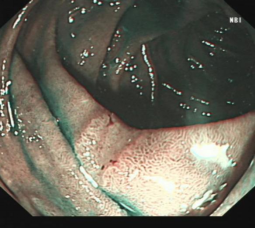

科室高清晰胃肠镜:正常的胃窦(线圈样腺管)和食管粘膜放大观察(IPCL)

消化道早癌的病例展示(经内镜手术或活检证实):

胃角的腺癌

胃窦的微小腺癌

胃窦印戒细胞癌

十二指肠降段早癌